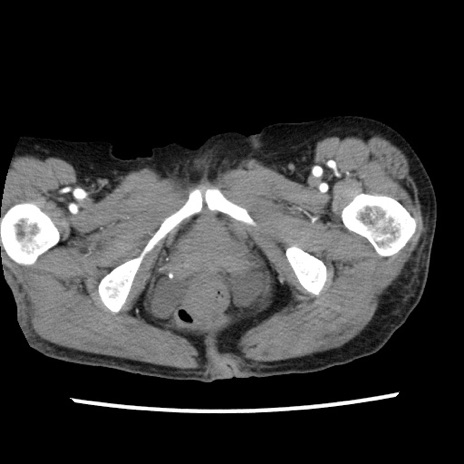

矢状断像